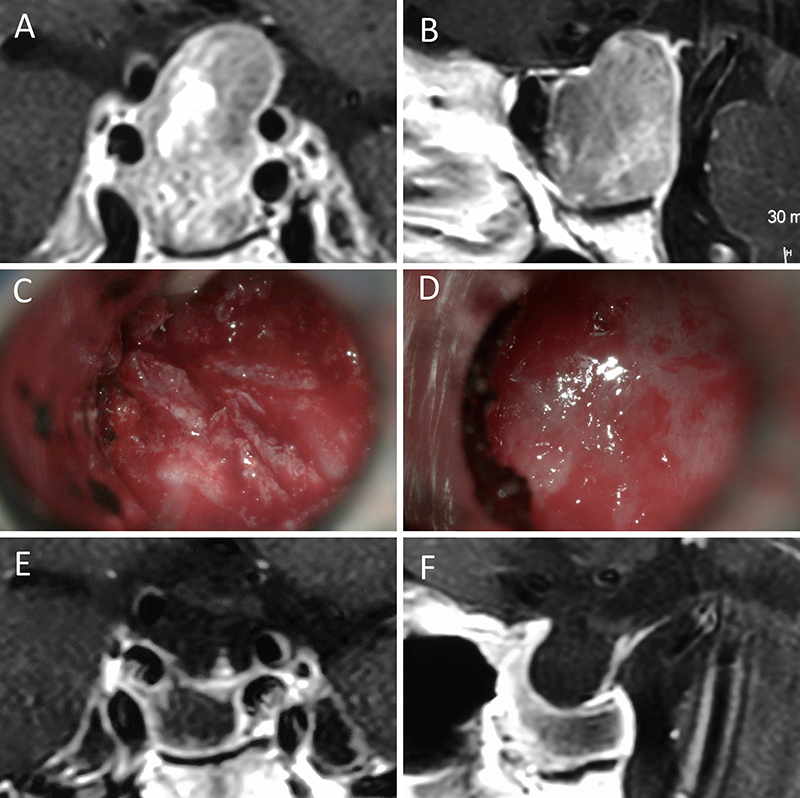

Figura 11: Microadenoma en una mujer de 36 años con Enfermedad de Cushing. Con remisión bioquímica tras la cirugía. A-B: RM preoperatoria; C-D: intraoperatorio; E-F: RM postoperatoria.

Figura 12: Microadenoma en una mujer de 26 años con Enfermedad de Cushing. Con remisión bioquímica tras la cirugía. A-B: RM preoperatoria; C-D: intraoperatorio; E-F: RM postoperatoria.

Figura 13: Macroadenoma en una mujer de 42 años con Enfermedad de Cushing. Con remisión bioquímica tras la cirugía. A-B: RM preoperatoria; C-D: intraoperatorio; E-F: RM postoperatoria.

Figura 14: Prolactinoma en un hombre de 32 años. Sufrió un cuadro de apoplejía pituitaria durante su tratamiento con cabergolina. Fue intervenido quirúrgicamente, evolucionando con normoprolactinemia. A-B: RM preoperatoria; C-D: intraoperatorio; E-F: RM postoperatoria.

Figura 15: Prolactinoma en una mujer de 19 años. Cursó con cuadro de resistencia a la cabergolina. Se decidió tratamiento quirúrgico y evolucionó con remisión bioquímica. A-B: RM preoperatoria; C-D: intraoperatorio; E-F: RM postoperatoria.

Enfermedad de Cushing

En una serie de 426 cirugías hipofisarias primarias en pacientes con enfermedad de Cushing, el Prof. Fahbulsh logró encontrar tumor durante la cirugía en un 86,6% (n=369) pacientes. En estos, se practicó una adenomectomía selectiva, obteniendo una remisión global del 75,9% (n=280) pacientes.35

Al evaluar las tasas de remisión en la misma serie, considerando el tamaño tumoral se evidencia la misma fue: del 77,9% para microadenomas y 59% en macroadenomas.35

Prevedello et al. reportó una remisión global del 88,6% en pacientes en los que se identificó el tumor en el intraoperatorio y una remisión del 11,4% en los que no se encontró el tumor.51

Gondim et al. publicaron una seria de 228 pacientes operados por vía baja, de los cuales 28 presentaron enfermedad de Cushing. De estos, se logró la remisión en un 75% de los microadenomas y un 62,5% de los macroadenomas.34

De todo lo antes dicho, se desprende que el tamaño tumoral y la identificación intraoperatoria son dos factores claves para lograr remisión luego de una primera cirugía.

En nuestra serie se alcanzó una tasa de remisión: global del 81%, para microadenomas del 84% y para macroadenomas del 71%. La tasa global y para microadenomas es equiparable a la publicada por equipos de referencia. La alta tasa de remisión en macroadenomas respecto a la literatura se explica por un sesgo estadístico (N reducido de pacientes con macroadenoma y enfermedad de Cushing).

Prolactinomas

En el pasado se discutía “tratamiento médico versus cirugía”; actualmente el tratamiento con agonistas dopaminérgicos se constituye como la primera línea y las indicaciones quirúrgicas se limitan a situaciones muy especificas.9 Sin embargo, un grupo significativo de pacientes finalmente son intervenidos quirúrgicamente por diversas causas (E.G. resistencia, intolerancia y reacciones adversas del tratamiento médico).36 De estos pacientes que son operados, analizaremos sus resultados.

Respecto a la tasa de remisión global, Jho et al. reportaron un 71%.38 En cuanto a la tasa de remisión según el tamaño, en una compilación de series publicadas, la tasa de normalización de PRL fue de 83% en microprolactinomas57 y 45.1% en macroprolactinomas1.

De lo antes expuesto, queda en evidencia que la cirugía ofrece excelentes resultados de tasa de normalización de prolactina en el caso de los microprolactinomas.9

Los pacientes con mayores chances de remisión son quienes presentan: niveles de PRL menores a 200 µg/l, tumores pequeños y amenorrea de corta duración. El hecho de tratarse de un macroadenoma disminuye cuantitativamente las probabilidades de remisión; y el hecho de tener extensión al seno cavernoso prácticamente la anula.21

El equipo de Viena, sostiene que la localización del tumor respecto a la glándula pituitaria es un factor asociado a remisión en microprolactinomas. En un reciente estudio, reportan una tasa de remisión en los adenomas centrales a la glándula significativamente mayor a la de los adenomas laterales a la glándula (87% vs 45%).46

En la presente serie la tasa de remisión global fue del 71%; mientras que la tasa de remisión según tamaño fue 100% para microadenomas y 50% para macroadenomas. Estas cifras pueden homologarse a la de las publicaciones enunciadas en este apartado. La alta tasa de normalización de la PRL obtenida en microprolactinomas se explica debido a que estos pacientes presentaron tumor central a la glándula y no lateralizado.